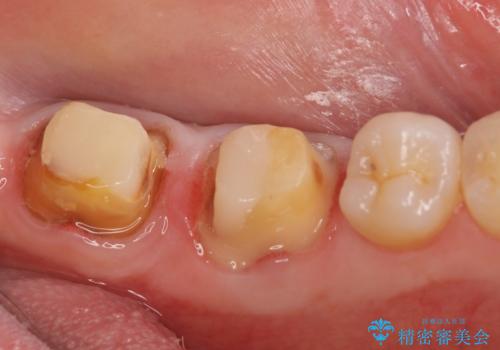

また左下6は遠心にあった歯茎より深い虫歯(縁下カリエス)の問題を解決するため、歯茎を下げる歯周外科手術を行いました。

歯周外科手術終了後、歯茎の回復を待ち左下6、7ともにオールセラミッククラウン(スタンダード)による補綴を行いました。

虫歯が進み歯茎より深くなってしまうと、虫歯を取り残してしまうリスク、樹脂の硬化の妨げ、補綴物の不適合、歯肉炎・歯周病のリスクの増大等様々な弊害が起こり得ます。

そのため当院では歯周外科手術(歯茎を下げる手術)や歯の挺出による、虫歯が歯茎より深いという問題の解決を推奨しております。